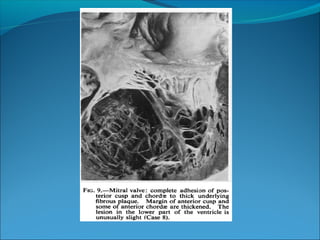

In 68% of patients, the posterior mitral leaflet is

involved and may be reduced to little more than a

fibrous ridge, permitting mitral regurgitation which

does not always produce the typical murmur on

auscultation

The valve leaflets otherwise remain intrinsically

normal unless there is bacterial or rheumatic

infection.